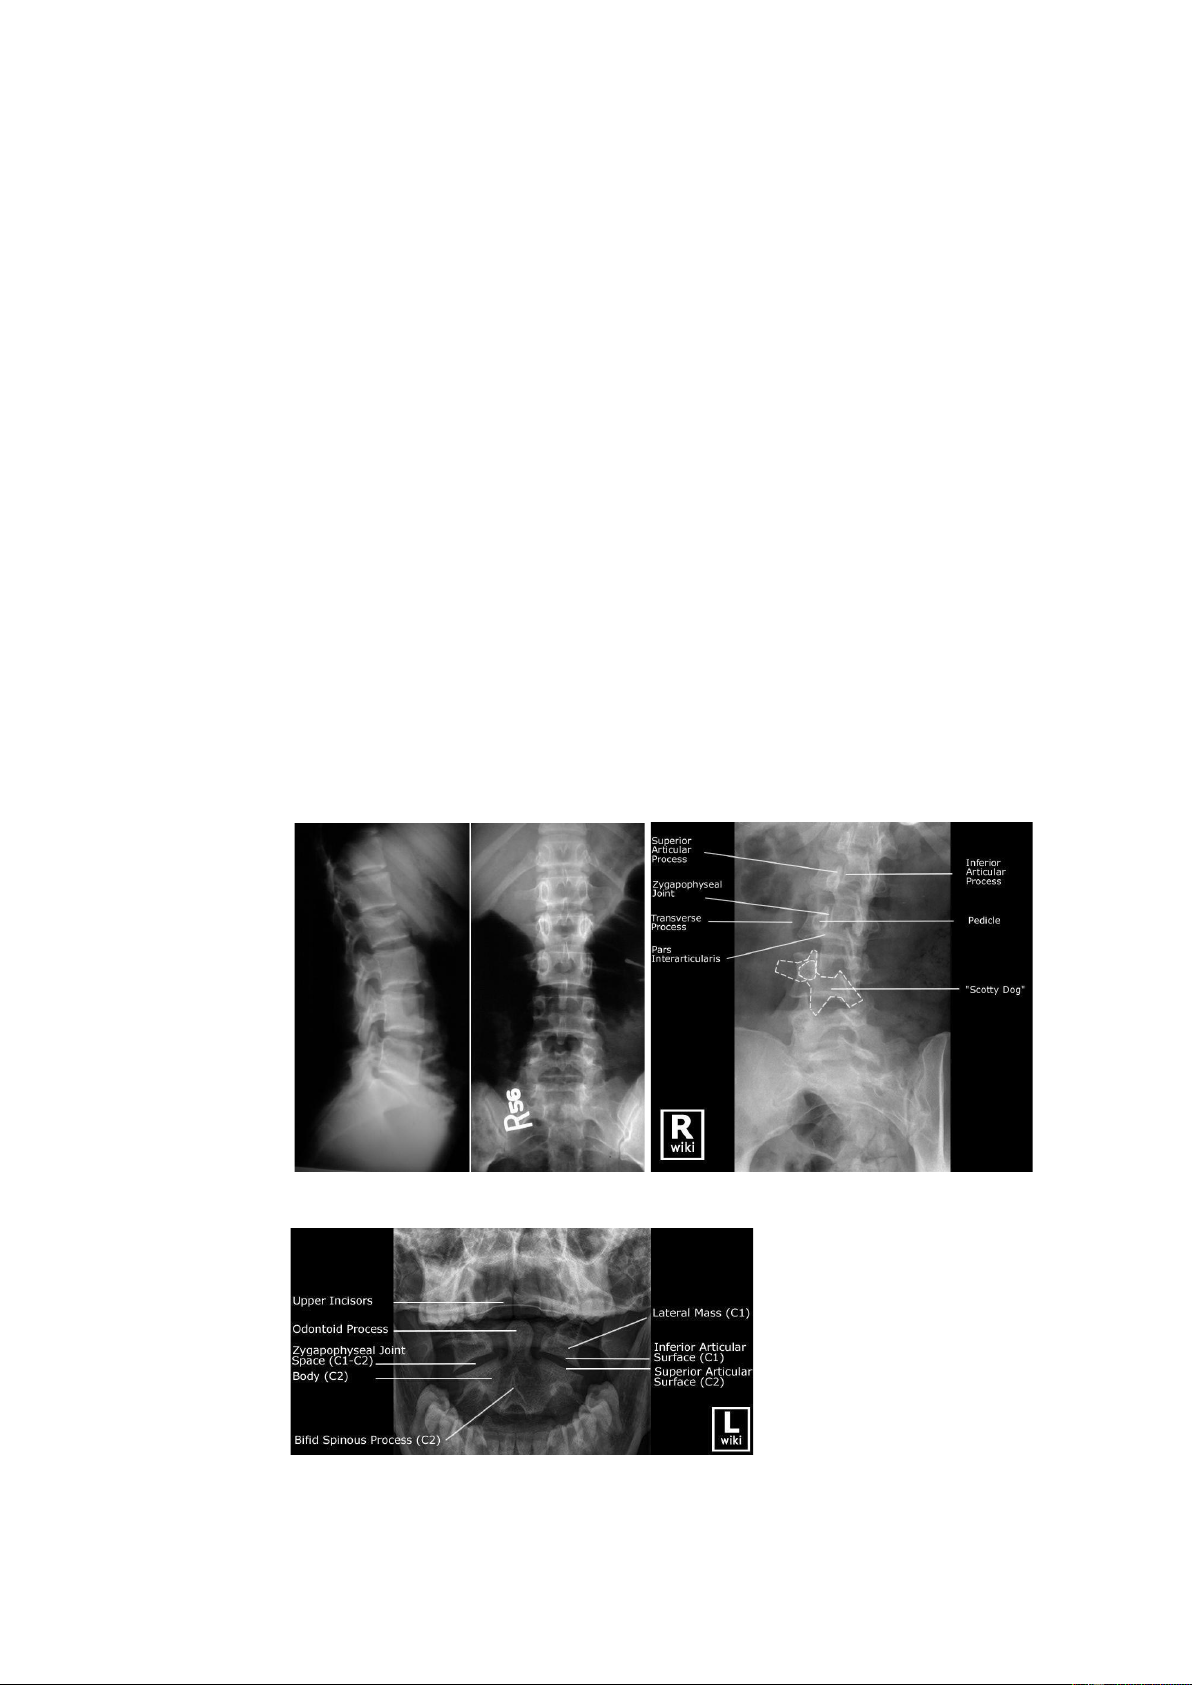

• Xquang thường: chụp phim thẳng, nghiêng, chếch 3/4 để kiểm tra

và đánh giá tổn thương xương. Nếu nghi tổn thương mỏm nha thì chụp xquang há miệng

Phim nghiêng, thẳng, chếch

Phim chụp há mồm bình thường lOMoAR cPSD| 39651089 Gãy mỏm nha